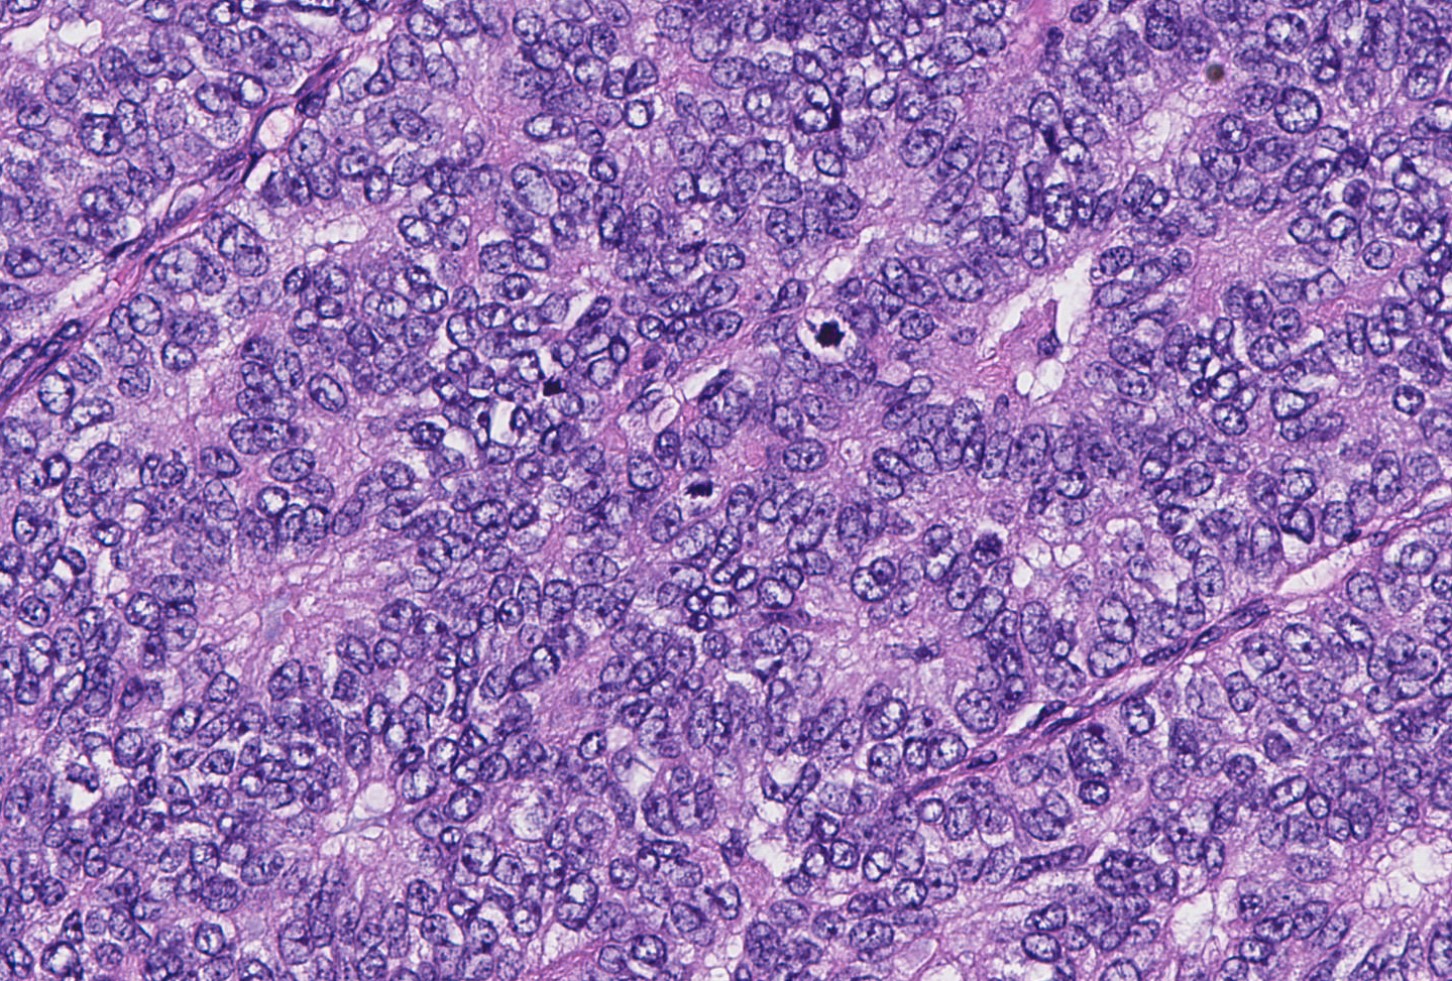

- Papillary tumor with pushing borders, may be within a cystically dilated duct, surrounded by a thick fibrous capsule (Histopathology 2008;52:20, Mod Pathol 2021;34:1044, Virchows Arch 2022;480:5)

- Delicate papillary fronds with fibrovascular cores lined by cuboidal to columnar epithelial cells with low to intermediate grade atypia

- Cribriform and solid architecture may be present

- Low mitotic activity (average 3 mitoses per 10 high power fields [HPFs]) (Am J Surg Pathol 2011;35:1)

- Most show complete lack of myoepithelial cells along the papillae and around the periphery of the tumor (Am J Surg Pathol 2006;30:1002, Am J Surg Pathol 2011;35:1)

Microscopic (histologic) images

Contributed by Kristen E. Muller, D.O. , Mariel Molina Nunez, M.D. and Julie Jorns, M.D. (Case #518)